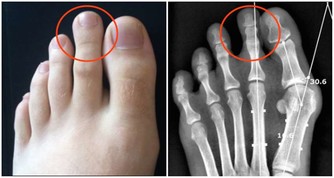

如果癌腫突出向直腸腔內生長,導致腸腔相對狹窄,

則排出的大便往往變細、變形,可呈扁形,有時變形的大便上附著一些血絲。